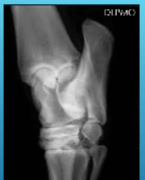

What is this lesion

OCD of the distal intermediate ridge of the tibia in the hock

OCD of the lateral malleolus in horse hock